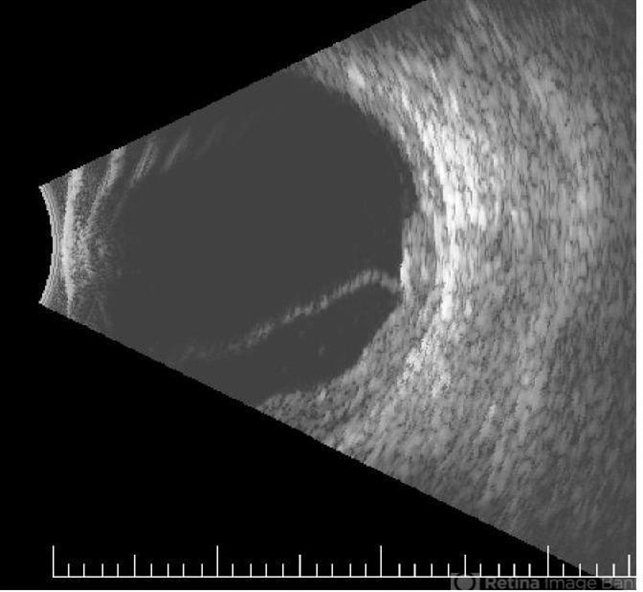

- B scan ultrasound, choroidal metastasis

- B-scan ultrasound image showing choroidal thickening and exudative retinal detachment in a patient with diffuse choroidal metastasis from breast carcinoma.